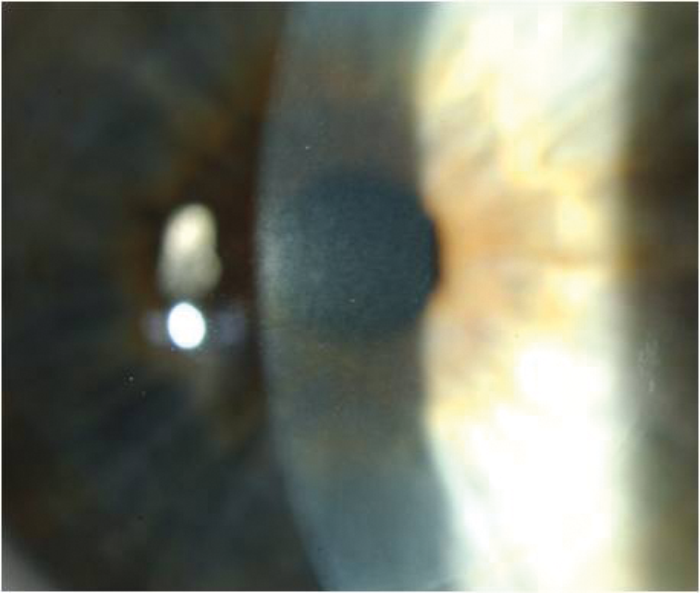

Figure 1: Gentian violet runs into the flap side cut (arrow) after irrigation with balanced

salt solution highlighting the point for a clean forceps entry with minimal epithelial trauma.

Epithelial ingrowth

In a review of 1000 consecutive cases [2], we identified a clear statistical association between epithelial trauma at surgery (or after), interface inflammation, and subsequent epithelial ingrowth secondary to inflammatory chemotaxis in from the interface. Gearing your primary surgical technique to avoiding epithelial trauma is the best way to avoid this sequence. A good tip is to mark the flap edge at the intended site of your forceps entry with gentian violet then irrigate with BSS before the flap lift. The BSS causes the gentian violet to run into the side cut promoting visualisation for a clean forceps entry.